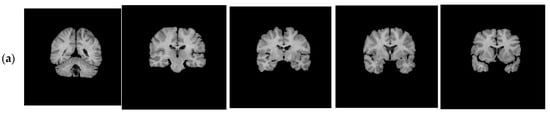

With regard to the T1-weighted MRI brain datasets, the performance of the HMRF-WOA was evaluated for 20 normal subjects. Figure 18 shows some slices of one subject (slices 20, 28, 32, 35, and 39); Figure 18a presents the initial slices images, (b) represents the ground truth segmentation, and (c) shows the HMRF-WOA segmentation results.

Moreover, Figure 18 illustrates the segmentation results of the proposed algorithm using MR brain images from the IBSR database. Figure 18a presents the slices of the original brain image; Figure 18b is the ground truth slice images; and Figure 18c shows the segmented brain MR images using the HMRF-WOA approach on the sample image of one subject. GM is shown in yellow, WM in red, CSF in green, and the background in blue.

Figure 18. Segmentation results of IBSR dataset: (a)—initial images; (b)—ground truth images; (c)—segmentation results.

Computers 13 00124 g018aComputers 13 00124 g018b